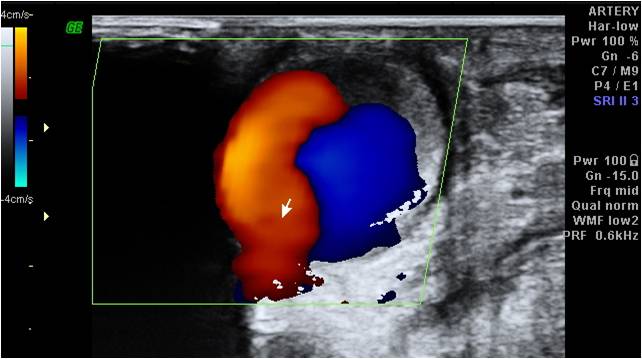

Dissecazione Della Carotide Interna (per Estensione Craniale ...

Direction of the flow is red-coded if blood flow approaches and blue- coded if blood flow moves away The flow with the pulsed Doppler, the position and the size of the area to explore . abdominal aorta US COLORDUPLEX ULTRASOUND COMBINES: a) B-mode information b) colorDoppler information ... Retrieve Content